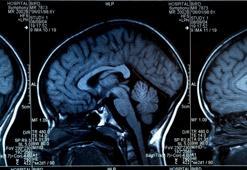

Beyninizi 6 ay daha erken yaşlandırıyor! Puanlar düştükçe risk artıyor

Uyku kalitesi düşünülenden çok daha büyük ve dönüşü olmayan sorunlara yol açabilir. Binlerce kişi üzerinde yapılan kapsamlı bir araştırma, bazı yaygın alışkanlıkların beynin biyolojik yaşını aylar hatta yıllar ileri taşıyabildiğini ortaya koydu. Uzmanlar, düzensiz gecelerin yalnızca yorgunlukla sınırlı kalmadığını aynı zamanda uzun vadede hafıza, dikkat ve zihinsel dayanıklılık üzerinde sessiz ama güçlü etkiler yarattığını vurguluyor. Peki, beyni 6 ay daha erken yaşlandıran alışkanlık nedir? Bilimsel araştırmanın sonucu ne oldu?

40 yaşındaki herkes yaptırmalı! Erken teşhis çok önemli

Beyinde hafıza ve bilişsel işlevlerin kapsamlı bir şekilde değerlendirilmesi olarak ifade edilen "kognoskopi"ye ilişkin konuşan Nöroloji Uzmanı Dr. Mehmet Yavuz, "Dünyada 60 milyon demanslı hasta var, bunların 45 milyonu alzaymır ve Türkiye’de 1 milyona yakın bunama vakası var. Belirtiler hafif olduğunda insanlar farkında oluyorlar ama çok ciddiye almıyor. O dönemde kognoskopi yaptırsa hadise başlangıç döneminde yakalanacak. 40 yaşındaki herkesin testi zaman zaman yaptırması gerekiyor çünkü beyin yoğunluğu çok sinsi bir hastalıktır. Kognoskopi yaptırma bilincine sahip olunmasını istiyoruz" dedi.